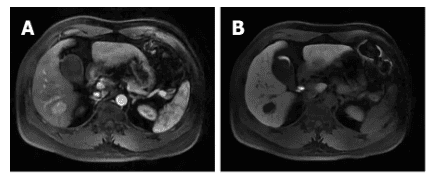

Đánh giá này cho thấy một bóng mờ tín hiệu bất thường dạng nốt ở S6 của gan có kích thước 2,5 cm × 2,0 cm × 2,3 cm với các cạnh mịn và ranh giới rõ ràng. Tổn thương biểu hiện dưới dạng giảm cường độ trên hình ảnh có trọng số T1 (T1WI) và tăng cường độ không đồng nhất trên hình ảnh có trọng số T2 (T2WI). Pha động mạch cho thấy tổn thương tăng cường đáng kể, trong khi pha tĩnh mạch cửa biểu hiện mức độ tăng cường thấp hơn so với nhu mô gan (Hình 1A và B ). Dựa trên các phát hiện hình ảnh, các bác sĩ cho rằng tổn thương là một nốt HCC.

Chụp cộng hưởng từ (MRI) khối u biểu mô quanh mạch gan (PEComa) ở một nam giới 37 tuổi: tổn thương nằm ở S6 cho thấy sự tăng cường rõ rệt trong thì động mạch gan (A), tăng cường viền ở thì muộn (B)